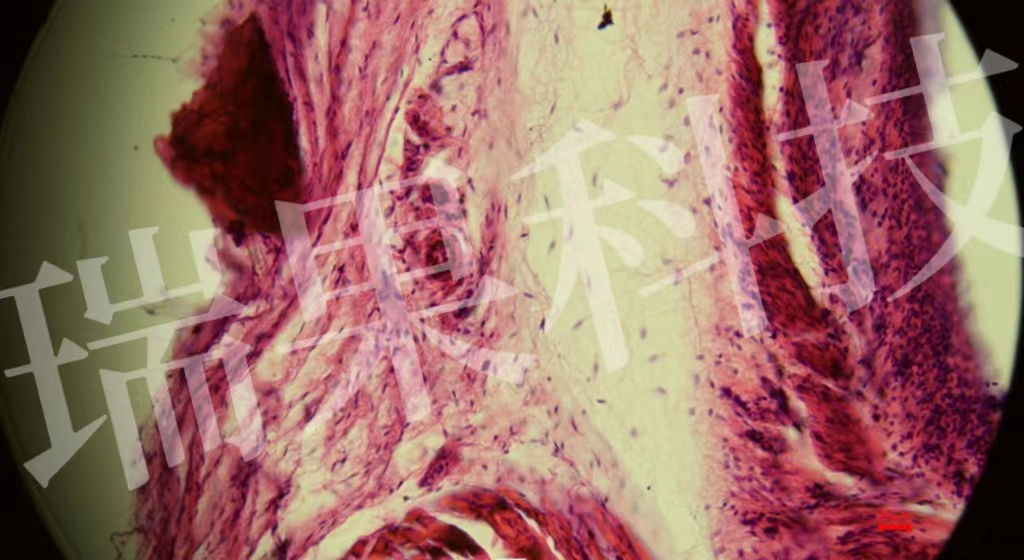

HE染色:苏木精 - 伊红染色法 ( hematoxylin-eosin staining ) ,简称HE染色法 ,石蜡切片技术里常用的染色法之一 。苏木精染液为碱性 ,主要使细胞核内的染色质与胞质内的核酸着紫蓝色 ;伊红为酸性染料 ,主要使细

HE染色:苏木精 - 伊红染色法 ( hematoxylin-eosin staining ) ,简称HE染色法 ,石蜡切片技术里常用的染色法之一 。苏木精染液为碱性 ,主要使细胞核内的染色质与胞质内的核酸着紫蓝色 ;伊红为酸性染料 ,主要使细胞质和细胞外基质中的成分着红色 。HE染色法是组织学、胚胎学、病理学教学与科研中最基本、使用最广泛的技术方法。

心1-1-20x